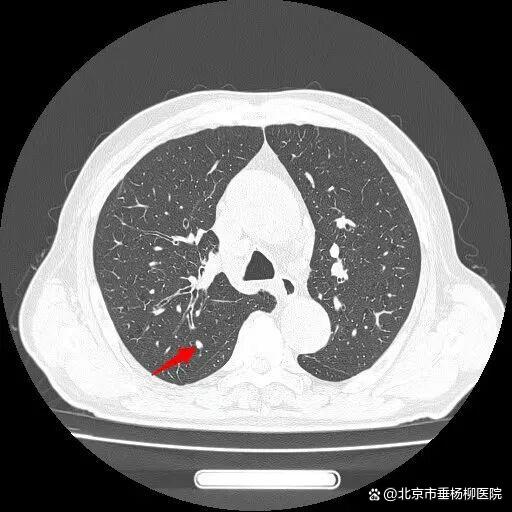

患者王大爷一年前体检发现右肺上叶有一约6×4mm结节,当时未予重视。一年后,他突然出现活动后喘憋症状,复查胸部CT显示右肺上叶后段出现约50×50mm不规则实性团块,影像学高度怀疑肺恶性肿瘤。

入院后,胸外科团队为患者行超声引导下经支气管针吸活检(EBUS-TBNA),病理结果提示为小细胞癌,并发现纵隔淋巴结转移。进一步全身检查显示,患者已出现肋骨及肝内多发转移,诊断为右肺上叶小细胞肺癌(cT3N2M1c IVB期)。

经过一个周期的治疗后,患者喘憋、咳嗽等呼吸道症状明显缓解,复查影像显示右肺上叶肿物显著缩小,疗效评估良好。这一结果让患者及家属重拾治疗信心,也为下一阶段治疗奠定了基础。